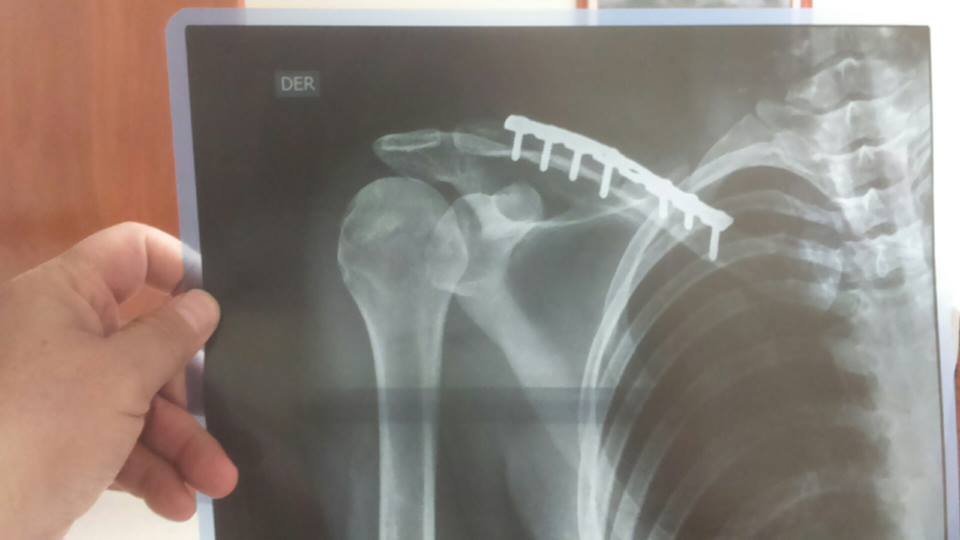

Así lo ha confirmado en las redes sociales Ortega de Miguel, que se toma con filosofía y optimismo este percance. La lesión, aunque no ha sido grave, le obligará a tomarse un descanso hasta que se encuentre plenamente recuperada. Este es el mensaje que lanzó en su cuenta de Facebook y la foto que adjunto, donde se puede observar la lesión:

“Desde aquí quiero hacer un llamamiento al tuerto que me esté mirando porque ya se ha cebado conmigo!!! Una caída tonta pero muy desafortunada mientras entrenaba en Chihuahua, (México) ha hecho que mi descanso veraniego se adelante. Y digo descanso porque así me lo tomo. Animada y con ganas para seguir, quizás era lo que necesitaba. Mientras seguiré aquí tres semanas más en el norte de México pero sin competir en Huatulco. Todo bien, aquí estoy muy bien cuidada gracias a Abraham y su familia pues no me he sentido sola en ningún momento. Sólo he sentido las ganas de volver rápido cuando se lo conté a mi madre y le ví preocupada. Pero esto es una experiencia más típica de triatleta, nada que no se pase.